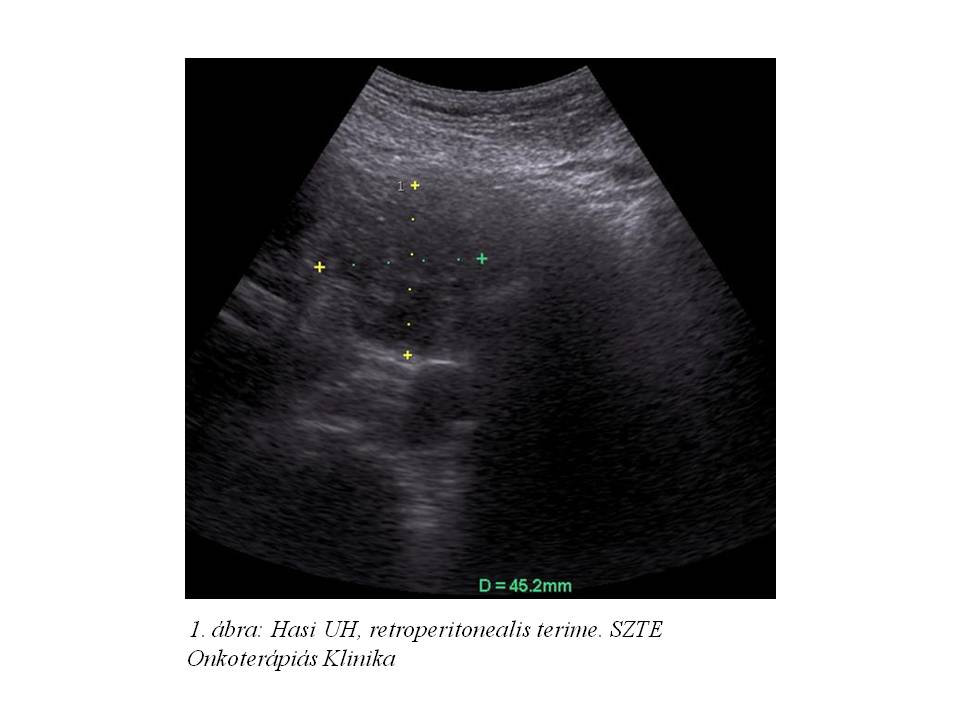

61 éves férfibetegünknél 2013 áprilisában indult kivizsgálás pancreatitisre hasonlító övszerű fájdalom és gyomorürülési zavarok miatt, melyek kb. 3 éve álltak fenn. Hasi UH vizsgálatán (1. ábra) egy nagy retroperitoneális terimét detektáltak, melyet has-kismedence CT vizsgálat (2. ábra) megerősített: a pancreas fej mögött egy 59x51x30 mm-es képlelet detektált, mely a pancreas fejjel összefügg. Mellkas RTG, gasztroszkópia negatív, CA 19-9 normális tartományban volt. UH vezérelt biopszia igazolta jól differenciált neuroendokrin malignus tumorát (immunfentipizálással béta-catein: 1+, KL1: 3+, chromogranin: 3+, synaptophysin: 3+, CD56: 3+, vimentin: -, Ki67: 15%), mely miatt 2013.05.28-án exploratív laparotomia történt az SZTE Sebészeti Klinikán. A folyamat inoperábilisnak bizonyult a környezeti infiltráltság miatt. Anamnéziséből kiemelendő, hogy az elmúlt évben 11 kg-ot fogyott (74 kg-ról 63 kg-ra).